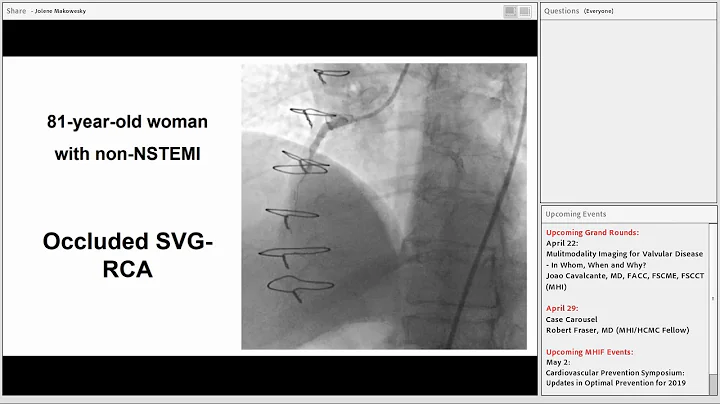

A patient was referred for PCI of a RCA CTO due to medically refractory angina. The RCA CTO had an ambiguous proximal cap, ...